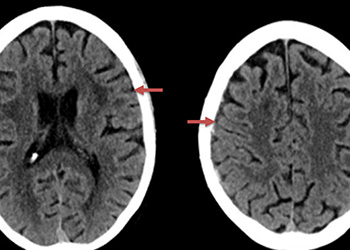

Brain:

Cerebral Metastases from Non-Small Cell Lung Cancer

Author: Xavier P. J. Gaudin D.O., F.A.C.O.S., Read More!